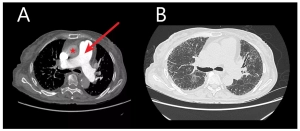

Inhaled treprostinil cuts mortality among patients of pulmonary hypertension associated with ILD: Study

Inhaled treprostinil cuts mortality among patients of pulmonary…